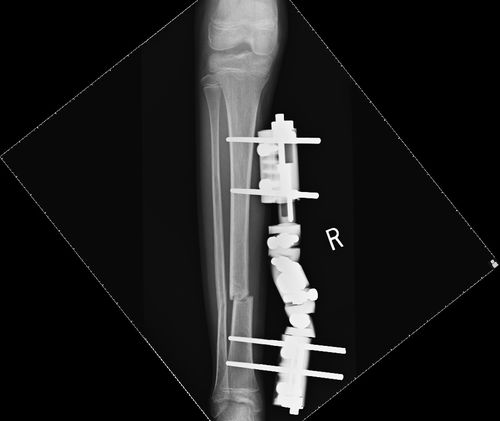

He therefore had external fixation applied.

He is now fully weight-bearing with his crutches and is expected to make a full recovery.